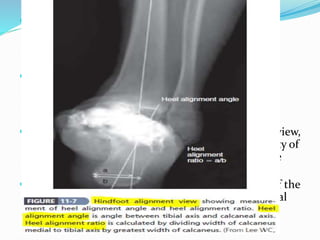

 Radiographic evaluation : The hindfoot alignment

view can assist in assessing deformity distal to the

ankle joint.

 Amount of joint space loss on the anteroposterior view,

coronal plane deformity should be assessed. Quality of

bone stock and any cysts or other defects should be

noted.

 On the lateral view, anteroposterior subluxation of the

ankle should be noted, as well as any tilt of the tibial

plafond